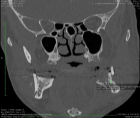

Sagittal split osteotomy (SSO) of the mandible is still an important part of orthognathic surgery, but “bad split” fractures that happen during the surgery are still a big problem. This report describes a rare case of bilateral bad split associated with highly compact mandibular bone (D1–D2 type) in a 53-year-old male undergoing mandibular advancement. The bone was too hard for the piezoelectric and rotary tools to work, and there was very little bleeding. This caused fractures in the cortex and lingual. Postoperative computed tomography confirmed the presence of highly dense bone, correlated with delayed healing and recurrence. Consistent pre-surgical CT scanning for an assessment of the density of the mandibular bone can provide essential information about the potential risk of the osteotomy procedure in the patient. Performing a careful bone quality and density examination pre-operatively will allow the surgeons to select the most appropriate instruments and surgical techniques that will fit the patient’s individual anatomy. Such a point escalates to being very significant when dealing with the geriatric population, as bone density increase can not only alter the fracture behavior but also the recovery process during and after surgery. The inclusion of regular CT-based bone density evaluations into the preoperative routine not only facilitates the anticipation of surgical difficulties but also results in safer and more efficient osteotomies.

Figure 4

Figure 1